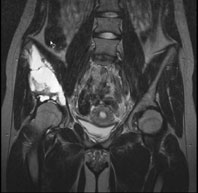

Die Röntgenuntersuchung von Becken/Hüfte zeigt eine septierte geographische Osteolyse in der Ala und im Korpus des Os Iliums rechts. Das Röntgenbild und die Aufnahmen der nachfolgenden MRI-Untersuchung sehen Sie hier: